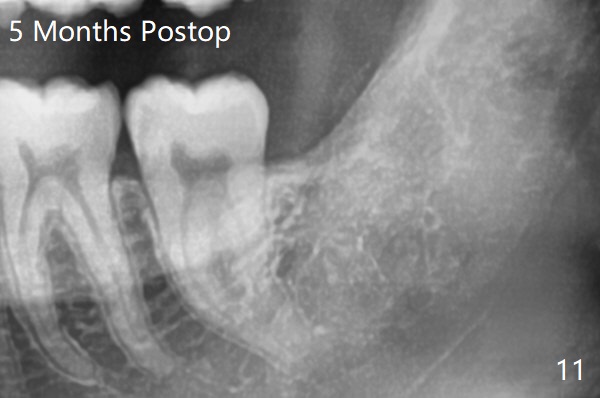

A 19-year-old man returns for #1,16,17 and 32 extraction (Fig.1,2). Because of horizontal impaction of #32 and no bone #31 distal post extraction (Fig.3 *), 3D bond (.5 cc) will be placed in the mesial socket of #32 (Fig.4 red), while Osteogen plug (1/2 (O)) in the distal one. Since there is no bony defect between #17 and 18 after extraction (Fig.5 *), a piece of Osteogen plug (cut half apical) will be inserted in #17 socket, whereas 2 small pieces of Osteogen plug placed in the apical portions (triangle and spindle shaped). Take posterior panoramic X-ray postop (bitewing type, CT format, not XV). There appears bone formation in the socket 5 months postop (Fig.10,11).

Since #32 sockets seem large, extending mesiobuccal (Fig.6), Bond Apatite (1 cc) is placed instead (Fig.7 B), covered by 1/3 of Osteogen plug (O) and sutured with 4-0 PGA. Extraction of #17 is also difficult. As 2 sockets are indistinct, a piece of Osteogen plug with split is placed (Fig.8) upside down (Fig.9 vs. Fig.5). There appears bone formation in the socket 5 months postop (Fig.10,11).